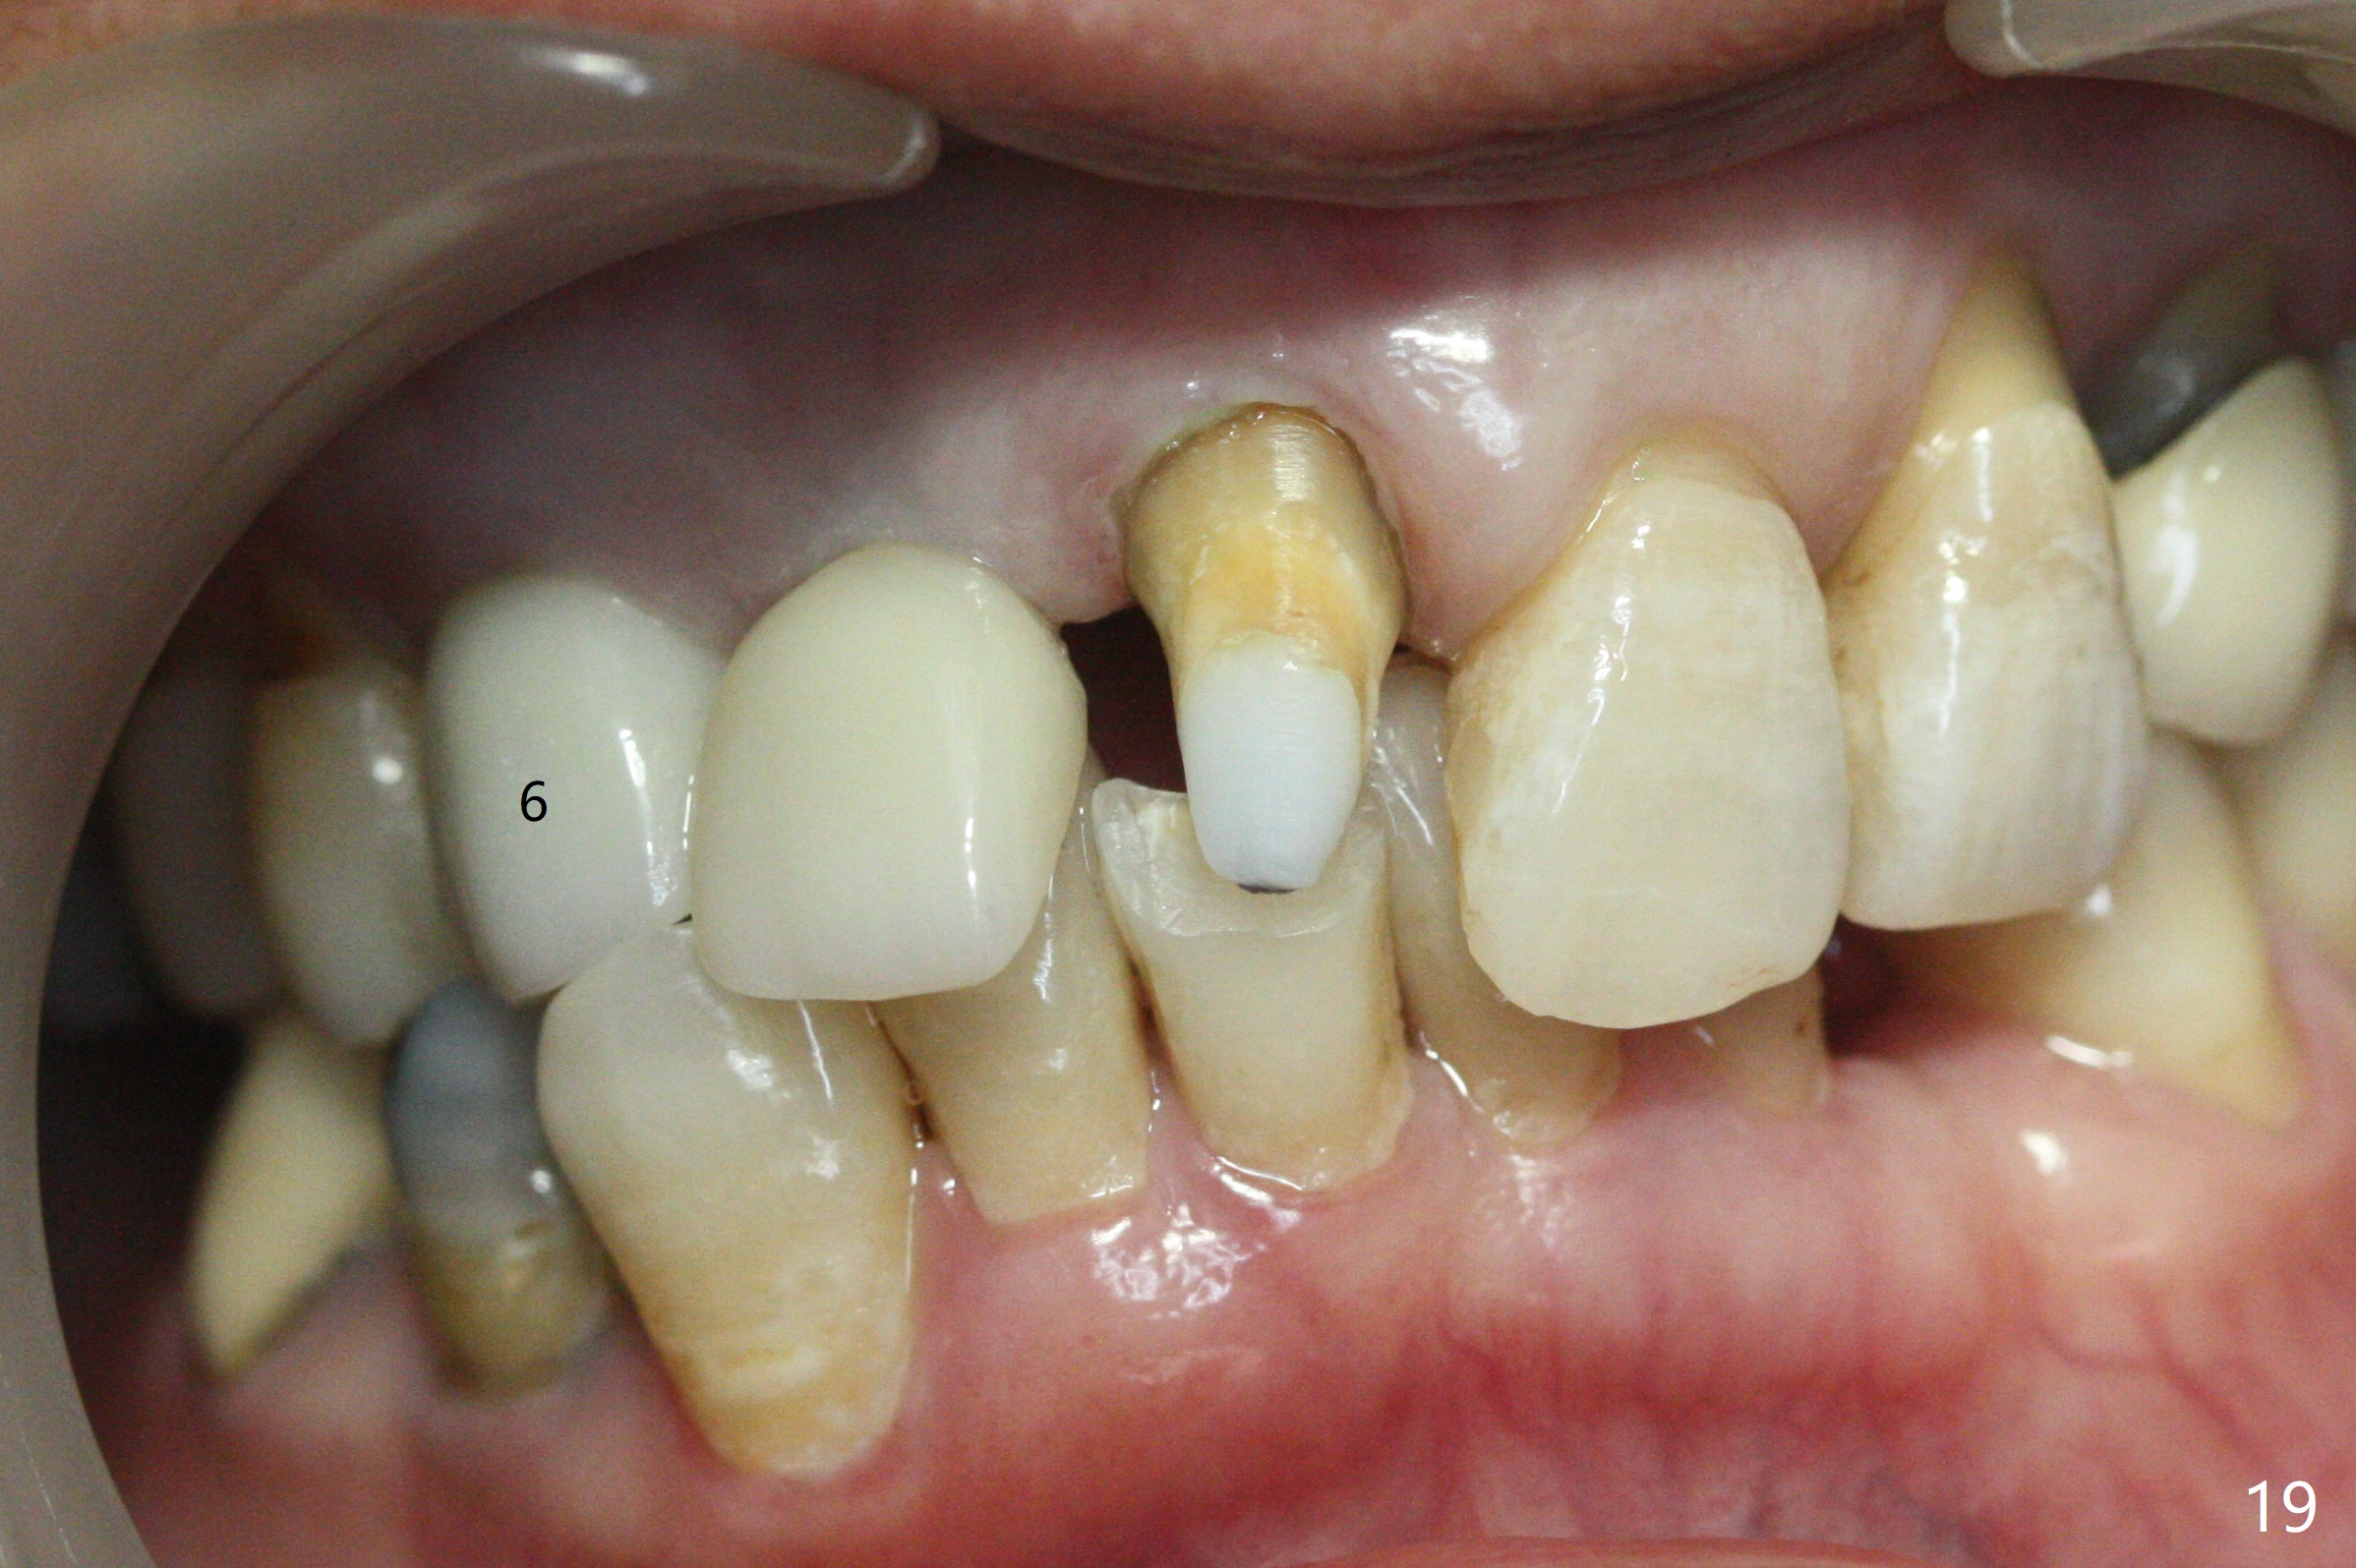

Since the ridge at #7 is ~ 4 mm, a 2.5x14 mm 1-piece implant is placed (Fig.8) after 1.2 mm (Fig.7), and 1.5 mm drills at 12 mm and 2 mm drill at 8 mm. Later the implant is placed deeper (Fig.10). There is no bone loss 7 or 12 months postop, respectively (Fig.11,12). After Diode gingivectomy, there is papillary formation (Fig.13). No provisional is provided after impression (with the abutment torqued at #6) for oral hygiene. With access holes at #6 and 7, crowns are bonded with minimal residual cement (Fig.14 <, which is removed later). There is no hard (Fig.15,16) or soft (Fig.17 *) atrophy 26 months postop, i.e., 13 months post cementation, due to the presence of socket shield (Fig.15 <, as compared to Fig.1). In fact the tooth #8 has mobility and fremitus (short root/poor crown/root ratio, Fig.16); occlusal adjustment is done 13 months post cementation. The crown is dislodged 2 years 1 month post cementation; a prefabricated post is being tried in (Fig.18). There is no atrophy, bone loss or infection at #6 (with socket sheath (*)) or 7 two years 5 months post cementation (Fig.20-27).